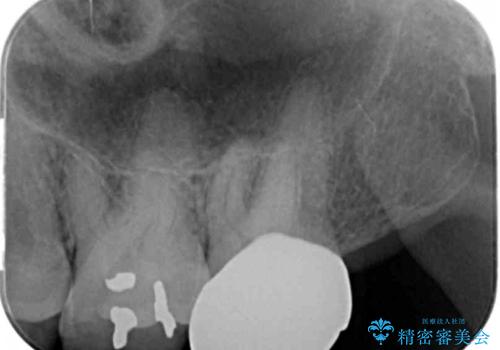

- 奥歯に物が詰まりやすいということが主訴で来院され、歯全体が虫歯になっていたので被せ物にて治療を行なった。

仮歯を装着した時点でものが挟まる症状は改善されました。

虫歯は綺麗に取り切れています。